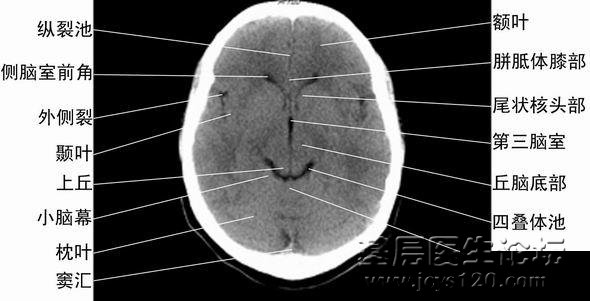

颅脑CT片详解